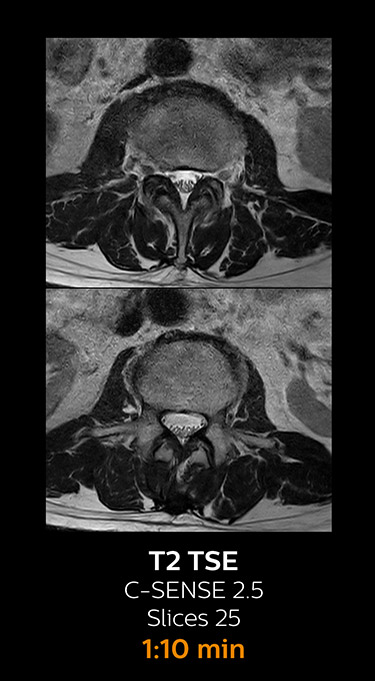

Fast MRI of cervical spine

With Compressed SENSE, the scan time for the routine cervical spine examination at KNC was reduced from 13:11 to 9:52 minutes, which corresponds to 25% reduction.

MRI examination of cervical spine with Compressed SENSE

MRI examination of the cervical spine with Compressed SENSE

Ingenia 3.0T CX

Scan time 9:52 min. (was 13:11 min. without Compressed SENSE)